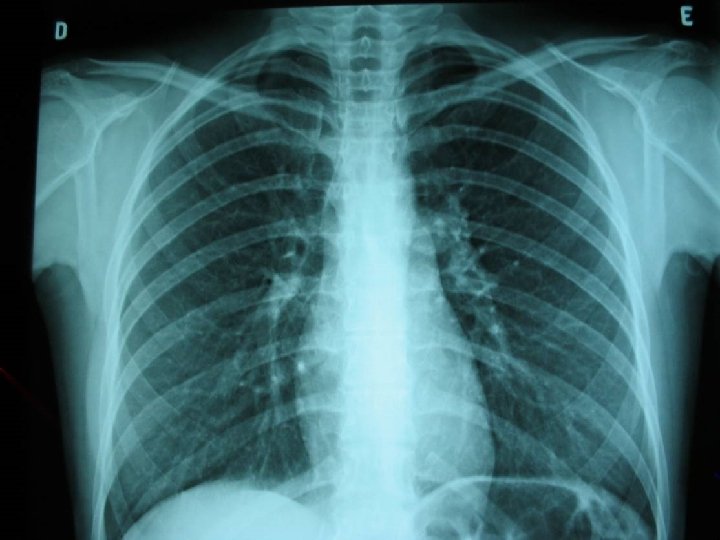

Critérios de qualidade 1. Centrado v Escápulas projetadas para fora dos campos pulmonares v Extremidades mediais das clavículas eqüidistantes da apófise transversa 2. Penetração adequada v Corpos vertebrais bem visíveis acima da sombra cardíaca v Atrás do coração, deve-se ver, no máximo, esboço da coluna torácica 3. Grau de inspiração v v Apnéia após inspiração máxima 9 a 11 arcos costais posteriores sobre os campos pulmonares

Radiograma padrão

Inspiração adequada Inspiração inadequada